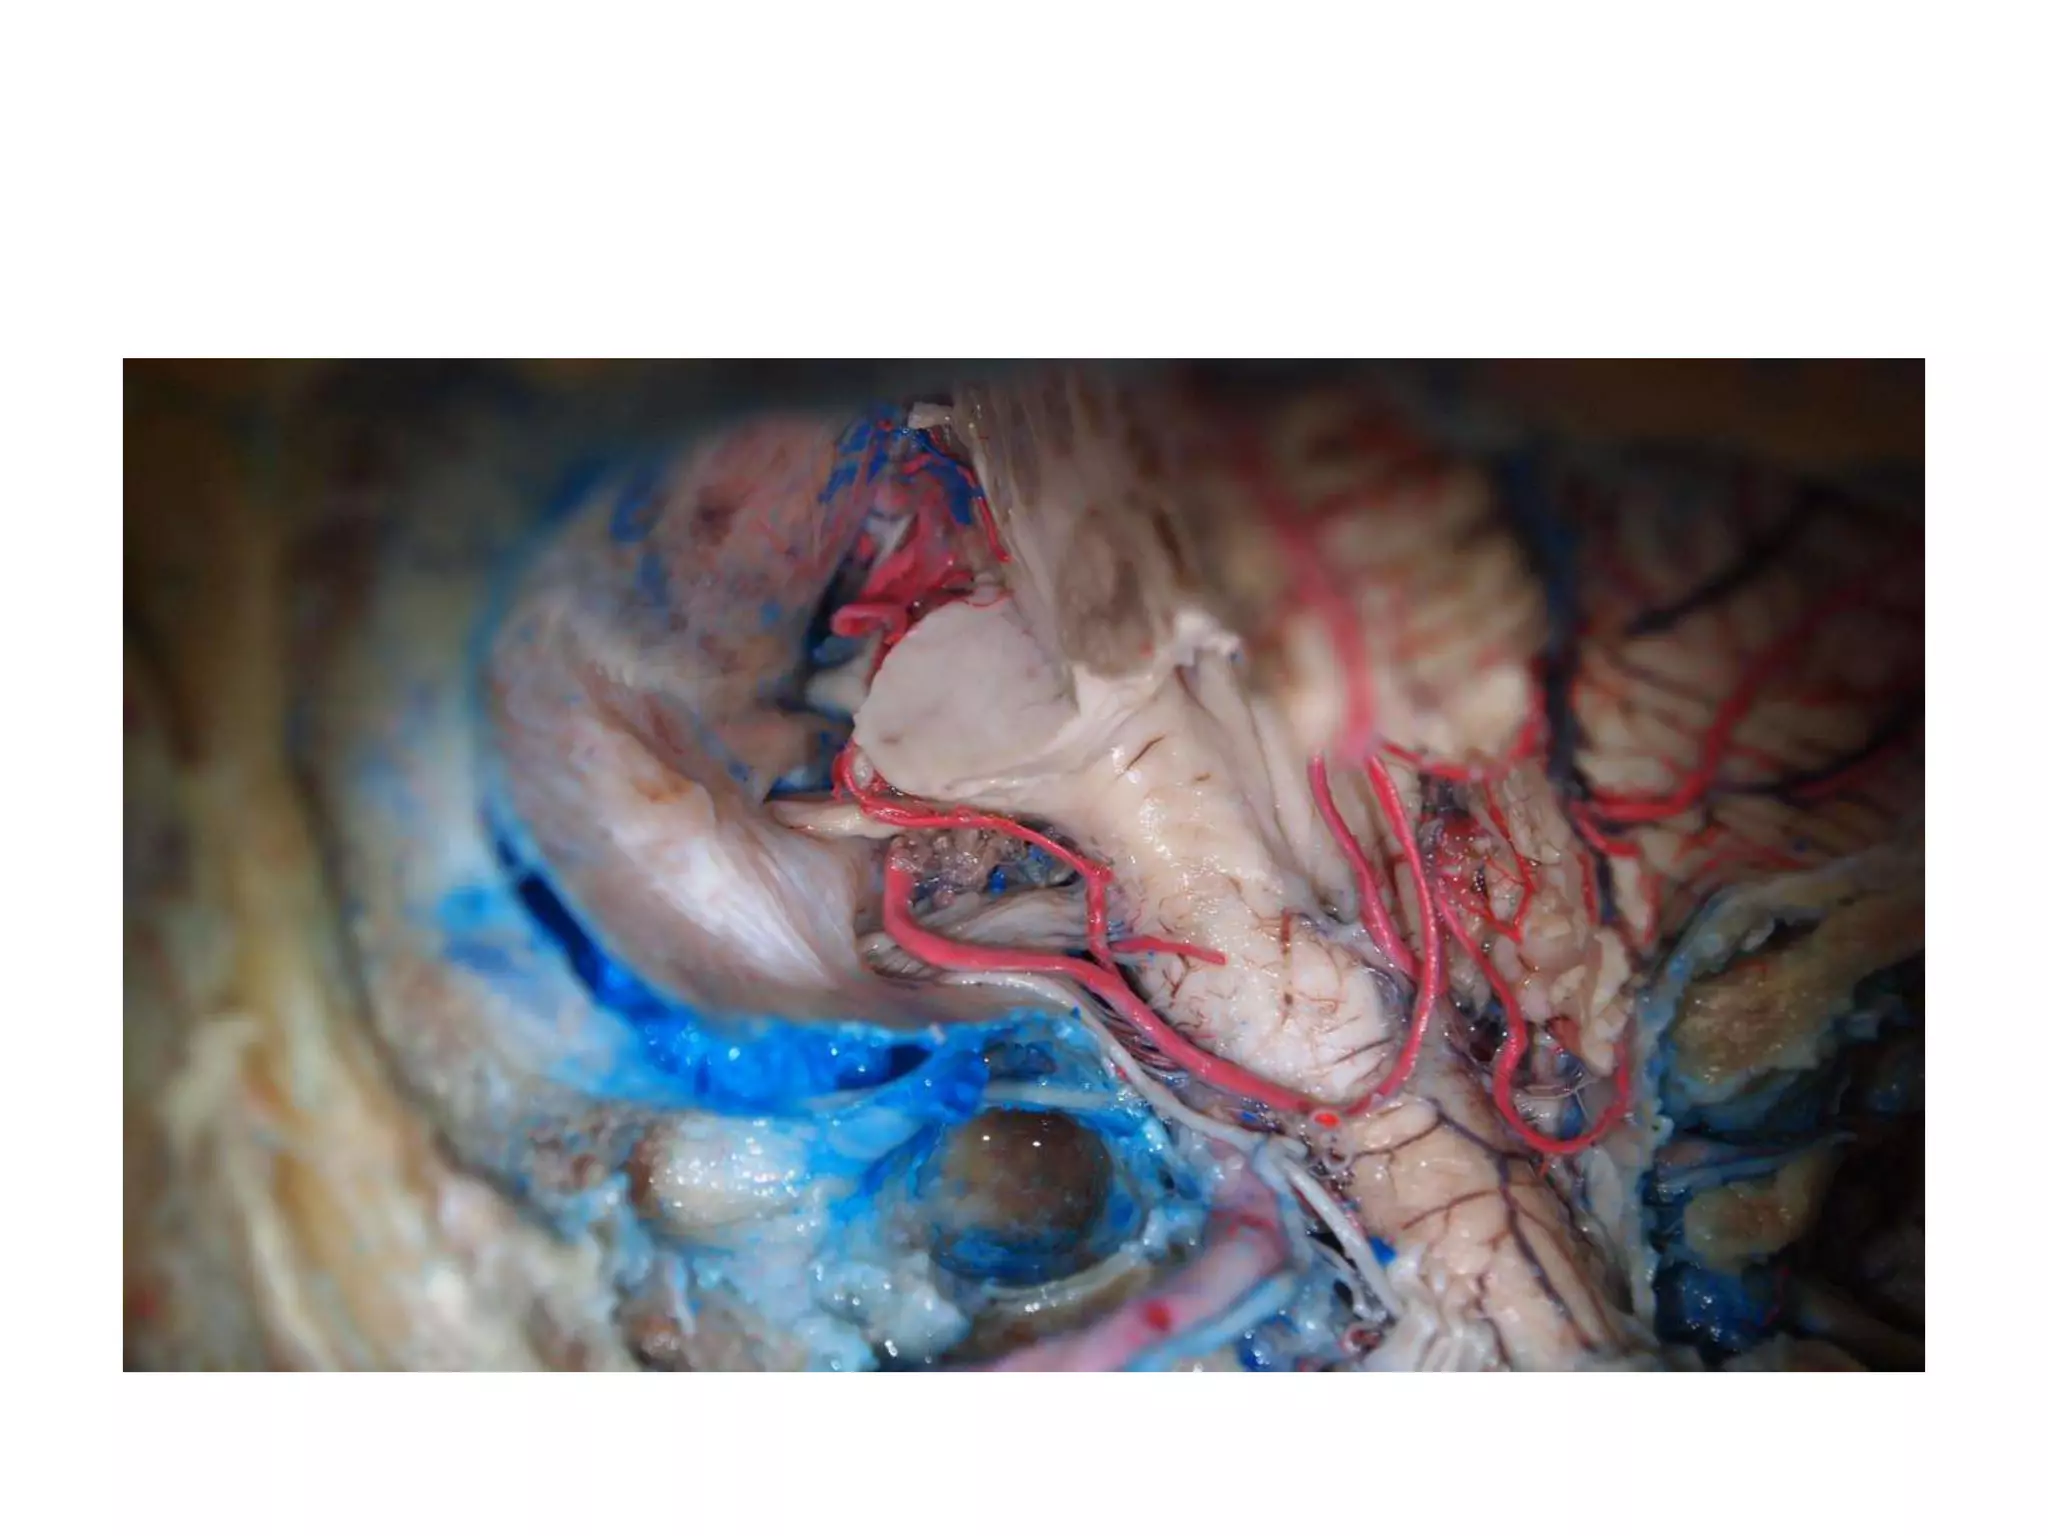

Cadaveric dissection image demonstrating the close anatomical relationship

of the posterior clinoid (PC) with both the intracranial carotid artery (ICCA)

and the posterior genu of the intracavernous carotid artery (P. CCA). AL,

anterior lobe of the pituitary gland; PL, posterior lobe of the pituitary gland;

BA, basilar artery.

green dotted triangle area for entry

of the endoscope into the interpeduncular fossa